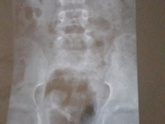

Девочки привет , вот 2 дня назад на рентген обнаружили спина бифида s1 s2 , переживание съедает в интернете посмотрела вообще до паники дошло , была у врача лечится сказала, но у неё наружу ничего не вышло ?♀️???есть которые сталкивались ? ?